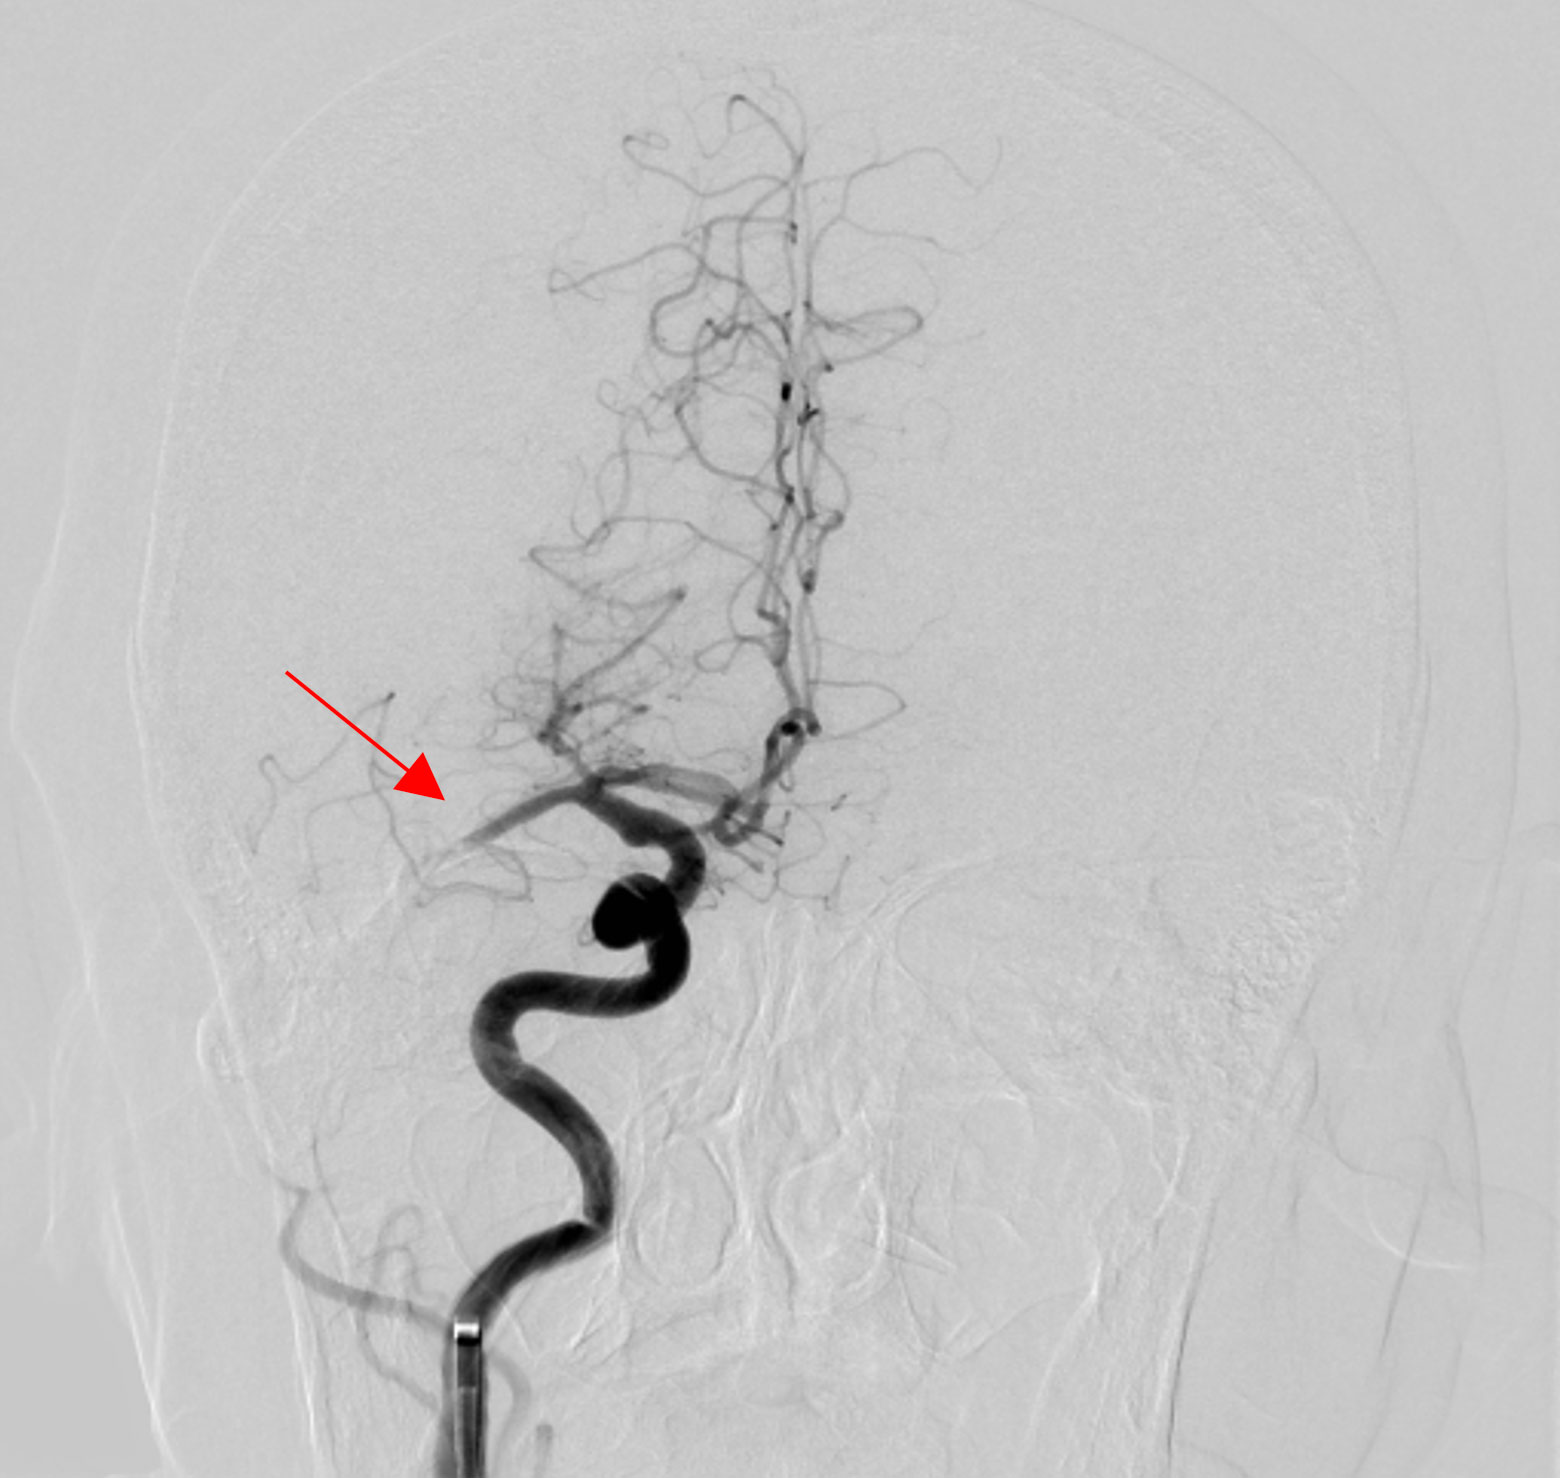

突然に頭痛、意識消失があり当院へ救急搬送され、血管内治療を行いました。(動脈瘤は赤矢印)

治療前

治療直後

1か月後には、症状もなく、歩いてご自宅に退院されました。